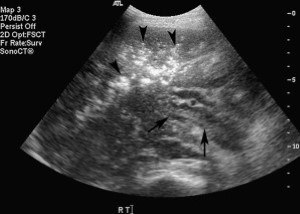

Siêu âm là phương tiện chẩn đoán hình ảnh nhậy để phát hiện khí trong tĩnh mạch cửa. Trên siêu âm thang xám, khí trong tĩnh mạch cửa biểu hiện là các chấm âm sáng, nhỏ chuyển động nhanh trong các nhánh tĩnh mạch (Hình 8). Trên siêu âm Doppler, các nhiễu ảnh tần số cao, giống như gai chồng vào sóng tĩnh mạch cửa là dấu hệu đặc trưng của khí trong tĩnh mạch (Hình 9) [16].

Hình 8. Khí trong tĩnh mạch cửa phát hiện tình cờ ở một phụ nữ 49 tuổi có tiền sử suy thận và HIV. Ảnh siêu âm thang xám cho thấy nhiều chấm tăng âm trong thân tĩnh mạch cửa (mũi tên) và các nhánh tĩnh mạch cửa. Các chấm tăng âm di động trong tĩnh mạch cửa có thể quan sát được bằng siêu âm thời gian thực. Khí trong tĩnh mạch cửa đã được xác định bằng CT (không trình bày).